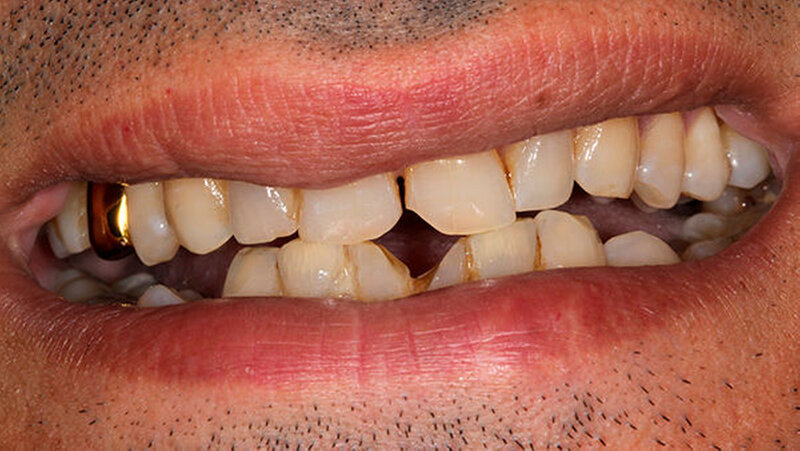

Oralchirurg Marcus Stoetzer arbeitete drei Monate lang im Feldlager der Bundeswehr in Mazar e Sharif - insgesamt behandelte er in Afghanistan 298 Soldaten. Die Bilder zeigen, aus welchem Grund sie zu ihm kamen.